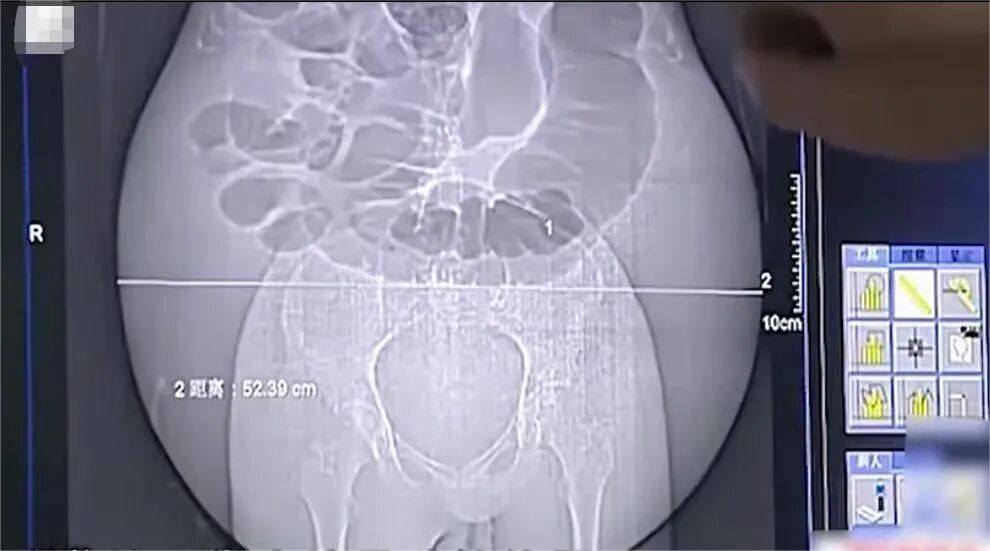

医生赶紧给彭细妹做了B超检查,可一看检查结果,众人傻了眼。

B超显示,彭细妹的肚子里全是液体,子宫、卵巢和肝脏等器官完全看不到。

原来,B超的穿透能力只有六七厘米,可彭细妹肚子厚达五六十厘米,因此,通过B超无法看清肚子里的情况。

医生又考虑给彭细妹做CT,可是她的肚子实在太大,远远超过了CT机设计的尺寸,根本进不去。